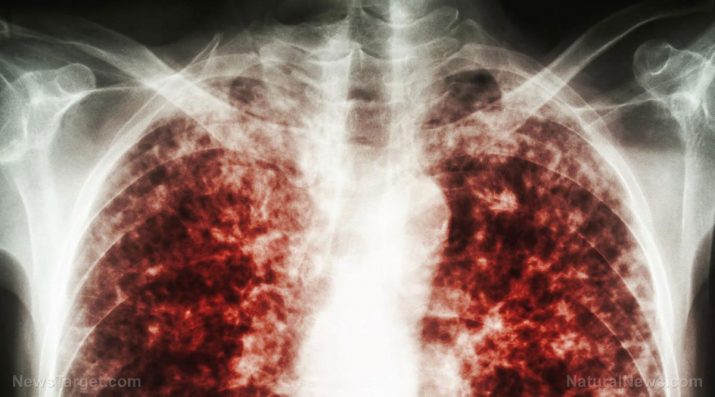

TB is an air-borne, contagious infection caused by Mycobacterium tuberculosis and is spread when an infected person coughs, sneezes or talks. Pulmonary tuberculosis (PTB) is an infection that occurs when M. tuberculosis attacks your lungs and may spread to other organs and can become lethal in many cases. (Related: Health experts warn untreatable tuberculosis threatens world.)